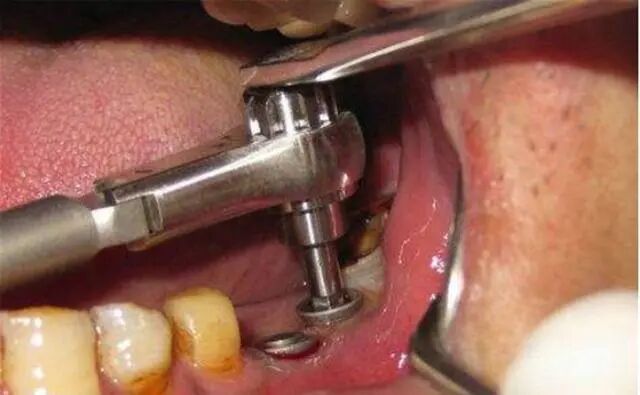

1、植入种植体

在牙槽骨上制备一个孔,植入人工种植体。让牙骨床内严密缝合,大约需要一个星期才能够拆线。然后就需要等待骨结合。